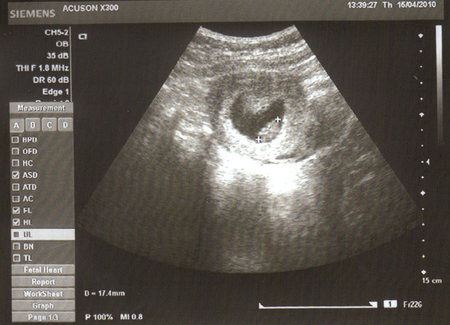

Сегодня наконец то нам сделали УЗИ...

Пузик так похож на гномика

у нас все хорошо, сердечко бьется, мы растем..

Странно но эта ч\б картинка и меня и мужа настроила на новый лад :) теперь мы видим что он там точно есть

Да пока и не понять на кого похож :) всего 17 милиметриков же пока